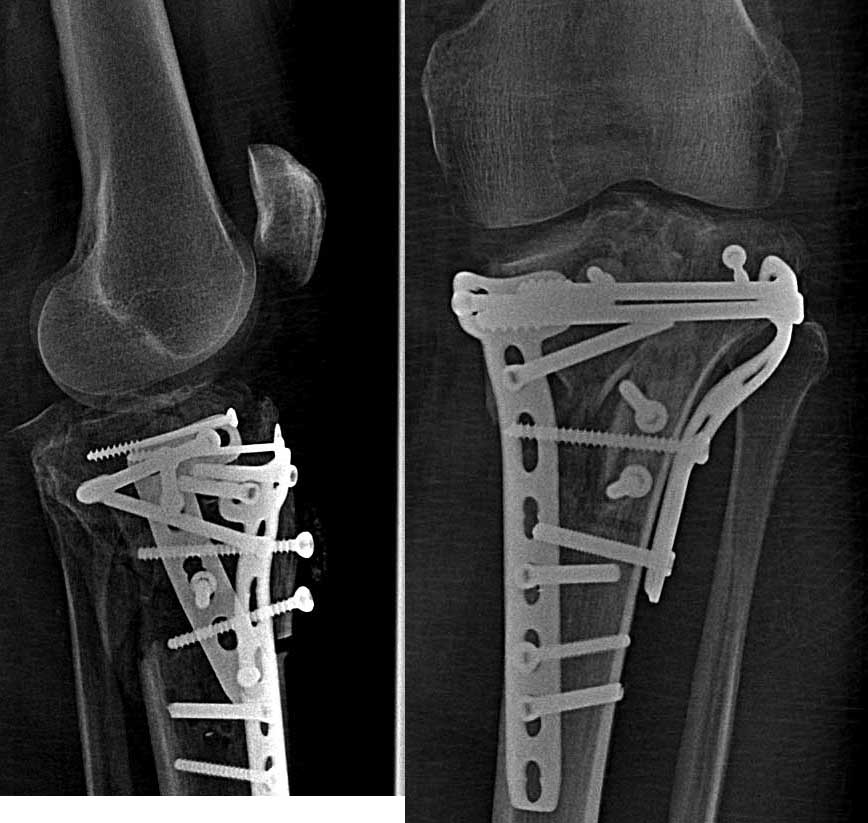

|  После операции |  Через 4 мес. |  После удаления | Травма бытовая от 14.08.13 – падение с высоты 2х метров, на полусогнутую левую ногу. Доставлен бригадой СМП в травмпункт, шинирован. В травипункте обследован клиничеки и рентгенологически – закрытый оскольчатый перелом внутреннего мыщелка левой большеберцовой кости со смещением и подвывихом голени кнаружи. Обезболен, наложена гипсовая шина. Направлен на стационарное лечение. При поступлении – ССВ за пяточную кость. Дообследован. 20.08.13 – остеосинтез большеберцовой кости пластинами LCP и винтами. Послеоперационное течение без особенностей. Заживление ран первично. 06.09.13 – выписан на амбулаторное долечивание с рекомендациями. В травмпункте – динамическое наблюдение. Ходьба 3 месяца без нагрузки на левую ногу. Фиксация жестким ортезом. В процессе реабилитации – контрактура сустава (разработанна), комбинированная нестабильность левого коленного сустава. Рентгенограммы в динамике – проседание отломков внутреннего мыщелка. 06.11.13 консультирован областным ортопедом - неправильно консолидирующийся перелом мыщелков левой большеберцовой кости. Genu Varum. Несостоятельность НБС, ПКС. Рекомендовано – фиксация ортезом, доведение нагрузки до полной. Через месяц решение вопроса об удалении металлоконструкции и пластика связок. В процессе реабилитации динамика слабоположительная. Дообследован. 15.01.14 – удаление металлоконструкции с левой большеберцовой кости. Послеоперационное течение относительно гладкое. Долечивание в травмпункте. ФТЛ. Ходьба с дозированной нагрузкой. Объективный статус: общее состояние удовлетворительное, сознание ясное, кожный покров физиологической окраски, периферические лимфоузлы не пальпируются. В лёгких дыхание везикулярное по всем полям, хрипов нет. Тоны сердца ясные, ритмичные, АД 140 и 90 мм .рт. ст. Ps 95 в 1 мин. Живот мягкий, безболезненный, печень по краю рёберной дуги, почки не пальпируются, Нарушения тазовых органов нет.

Локально: Стойкий болевой синдром при нагрузке и движениях в левом коленном суставе. Ходит на костылях с незначительной нагрузкой на ногу. При передвижениях использует жесткий ортез. Кожа левого коленного сустава физиологической окраски. Отек незначительный, контуры левого сустава сглажены по сравнению с правым. Выпота всуставе нет. Послеоперационные рубцы в\3 левой голени, без признаков воспаления. Положительные тесты «переднего выдвижного ящика», «Pivot shift», «Jerk». Неврологических и ангиотрофических расстройств дистальней нет. Рентгенографическое обследование в динамике прилагаю. КТ, МРТ - нет.

Внутренний мыщелок нерепонирован изначально.

Резюме: сначала восстановите анатомию костных структур. Возможно ли? - не на 100%, так как есть невосполнимые потери собственно суставной поверхности. Метафизарные дефекты требуют костной пластики больше с точки зрения биологической поддержки, чем механической. Метафиз после удаления пластин выглядит "измученным" и не очень здоровым.

связки на таком варусе сложно оценить. Для определения дальнейшей тактики без СТ не обойтись, не очень понятен фрагмент сзади. А так, реоперация - элевация внутреннего мыщелка с костной пластикой и опорной пластиной

О типичных ошибках в лечении переломов тибиал плато по Schatzker IV я говорил во всех прежних выступлениях. Не было нужды фиксировать интактную латеральную колонну пластиной, потому что удержать медиальную колонну без фиксации медиального мыщелка невозможно. Пластина даже с угловой стабильностью не удержит от варусных сил!

Все внимание на медиальной стороне, и здесь кроме фиксации перелома медиального мыщелка надо подумать как восстановить типичное смещение кзади. Одна медиальная пластина не может предотвратить скольжение, потому что винты находятся в другой плоскости. Через медиальный фрагмент прошли минимум винтов и не создан противоскользящий эффект мыщелка задней пластиной.

Не восстановлен дефект кости, а дефицит привел к несращению. Костная пластика метафизарных отделов, кроме биологии, создает структуральную подержку, иначе быстро уходит в коллапс.

Надо сделать сравнительные снимки конечности больших размеров и КТ. Цель операции - создание конгруентности сустава на одном уровне. 3Д позволит увидеть смещение и остеотомия медиального мыщелка с разворотом будет достаточным, чтобы уйти от варуса. Одна или две пластины в зависимости от достигнутой коррекции, а для дефекта графт. Временный наружный фиксатор (аппарат Илизарова) для профилактики варуса.